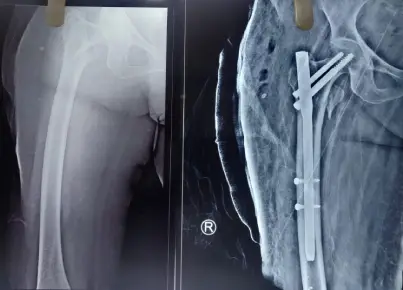

Dr. Keerthivasan Contact number WhatsApp